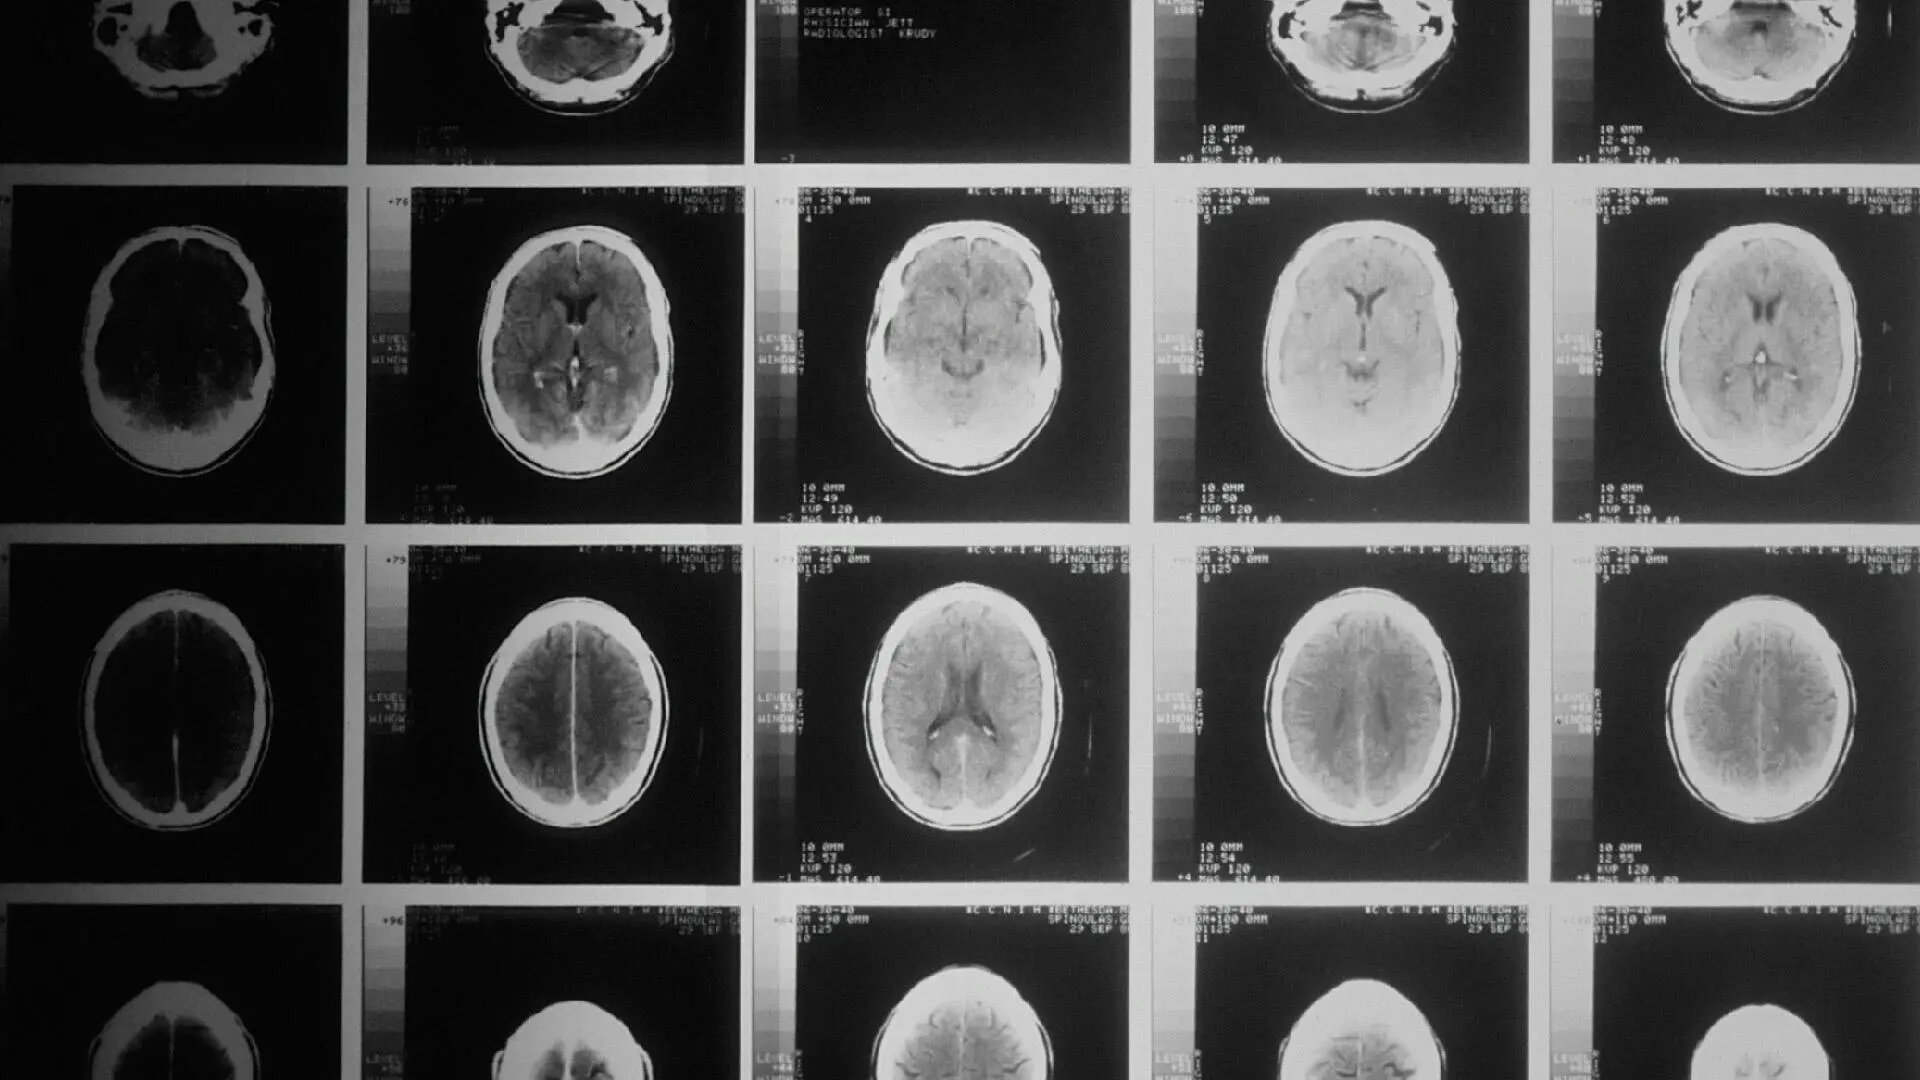

Les avancées en matière d'intelligence artificielle (IA) dans le domaine de la santé peuvent améliorer la vie des êtres humains du monde entier et accélérer la recherche dans des domaines essentiels. Grâce à une utilisation réfléchie et responsable de l'IA, les médecins peuvent prendre de meilleures décisions, la gestion des soins peut être optimisée et des vies peuvent être sauvées.